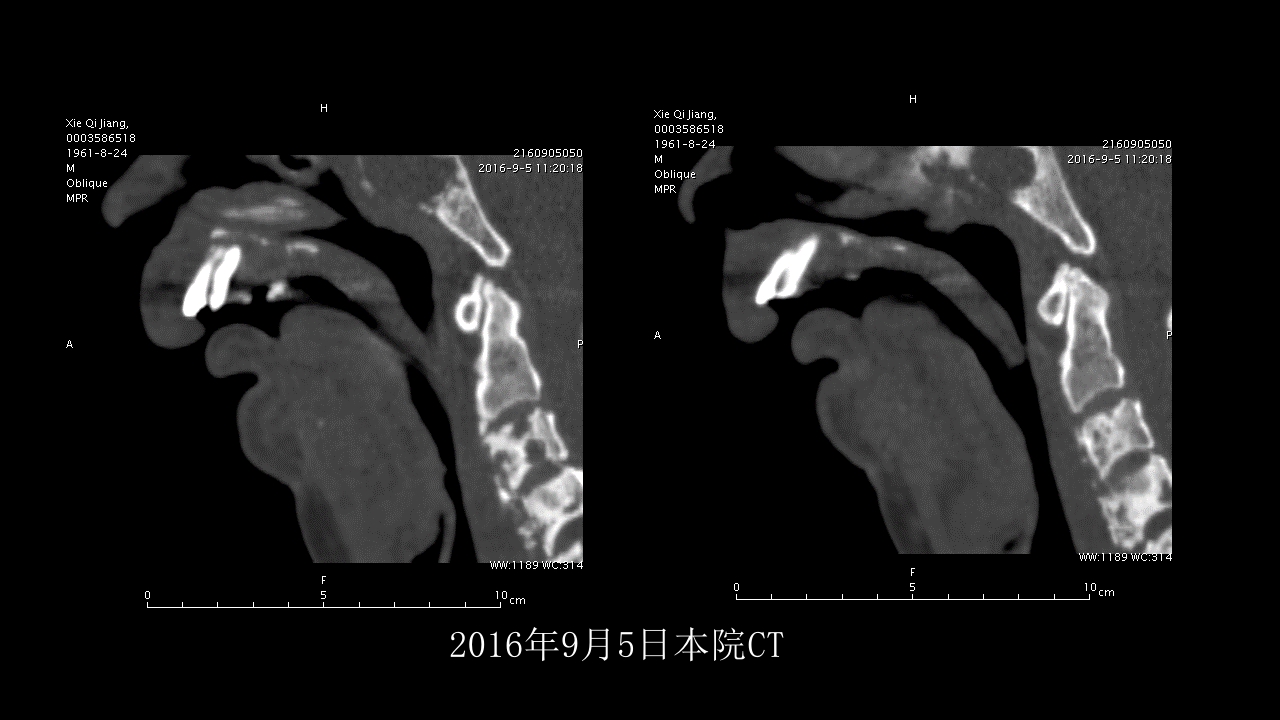

没有见过的弥漫性的骨质破坏